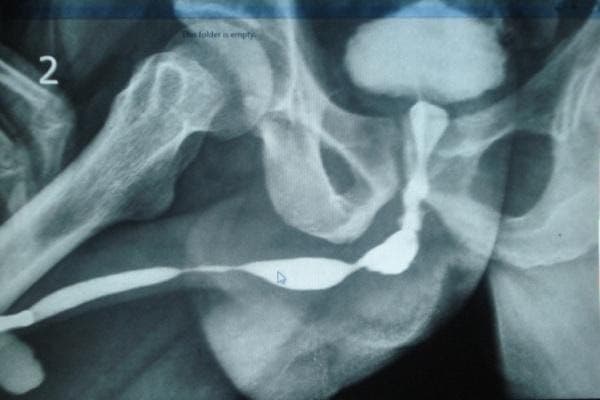

4. Retrograde / Ascending Urethrogram (RGU/AUG)

A radiological investigation in which a radio-opaque dye is injected into the urethra and the x-ray snap is taken.

5. Micturating / Voiding Cystourethrogram (MCUG/VCUG)

A radiological investigation in which the bladder is filled with a radio-opaque dye using a small tube and x-ray snaps are taken while the patient passes urine.